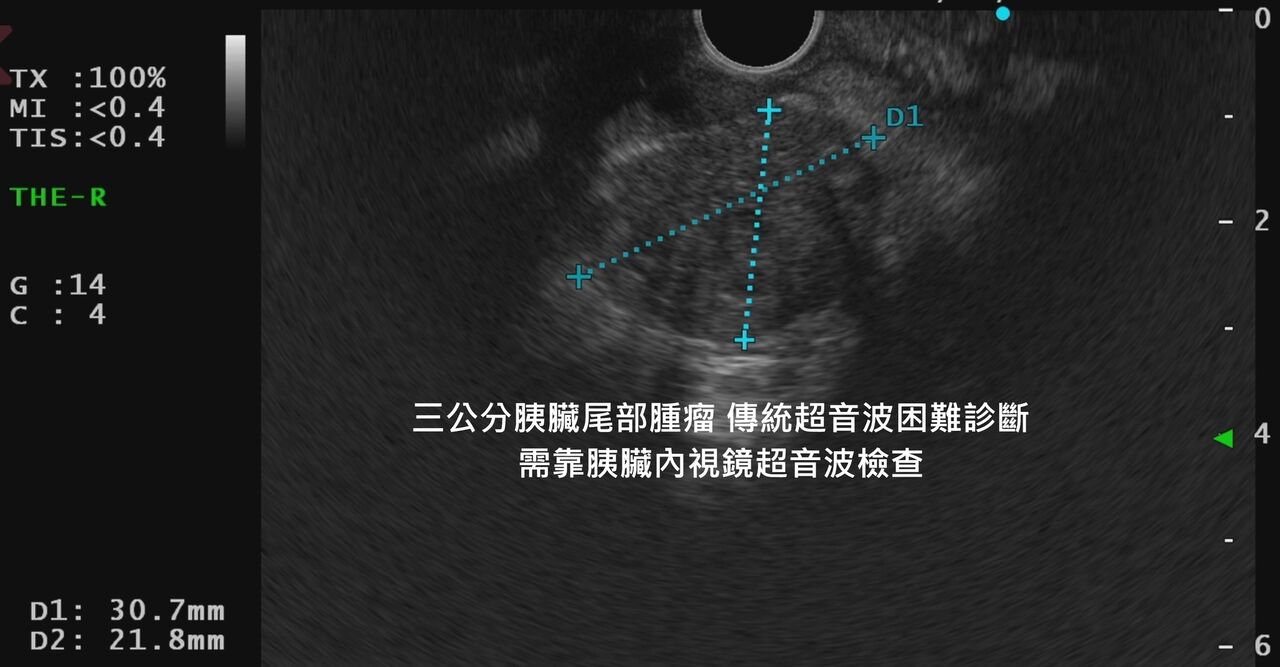

▲醫師透過胰臟內視鏡超音波檢查,發現3公分胰臟癌腫瘤。(圖/翻攝林相宏臉書)

林相宏指出,初步先照腹部超音波,還真的覺得胰臟沒什麼特別,不過胰臟尾部腫瘤真的很難用超音波照出來,因為前面很多胃腸空氣擋住;馬上安排胰臟內視鏡超音波檢查,鏡頭一掃答案不用3秒鐘就出來了,一個非常典型胰臟癌腫瘤,超過3公分了,趕緊轉診評估手術,希望還來得及。